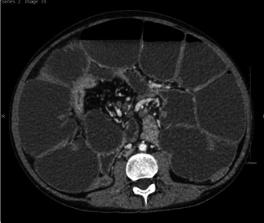

电解质紊乱得到纠正后,开始规律饮食。用组织转谷氨酰胺酶IgA进行乳糜泻筛查和粪便PCR病原体检测均为阴性。腹部X光显示肠梗阻,可能伴有部分肠梗阻。计算机断层扫描显示炎性改变,回肠末端壁增厚,狭窄7cm(图1),引起部分小肠梗阻。咨询了胃肠病学和外科团队。

图1、CT显示小肠梗阻